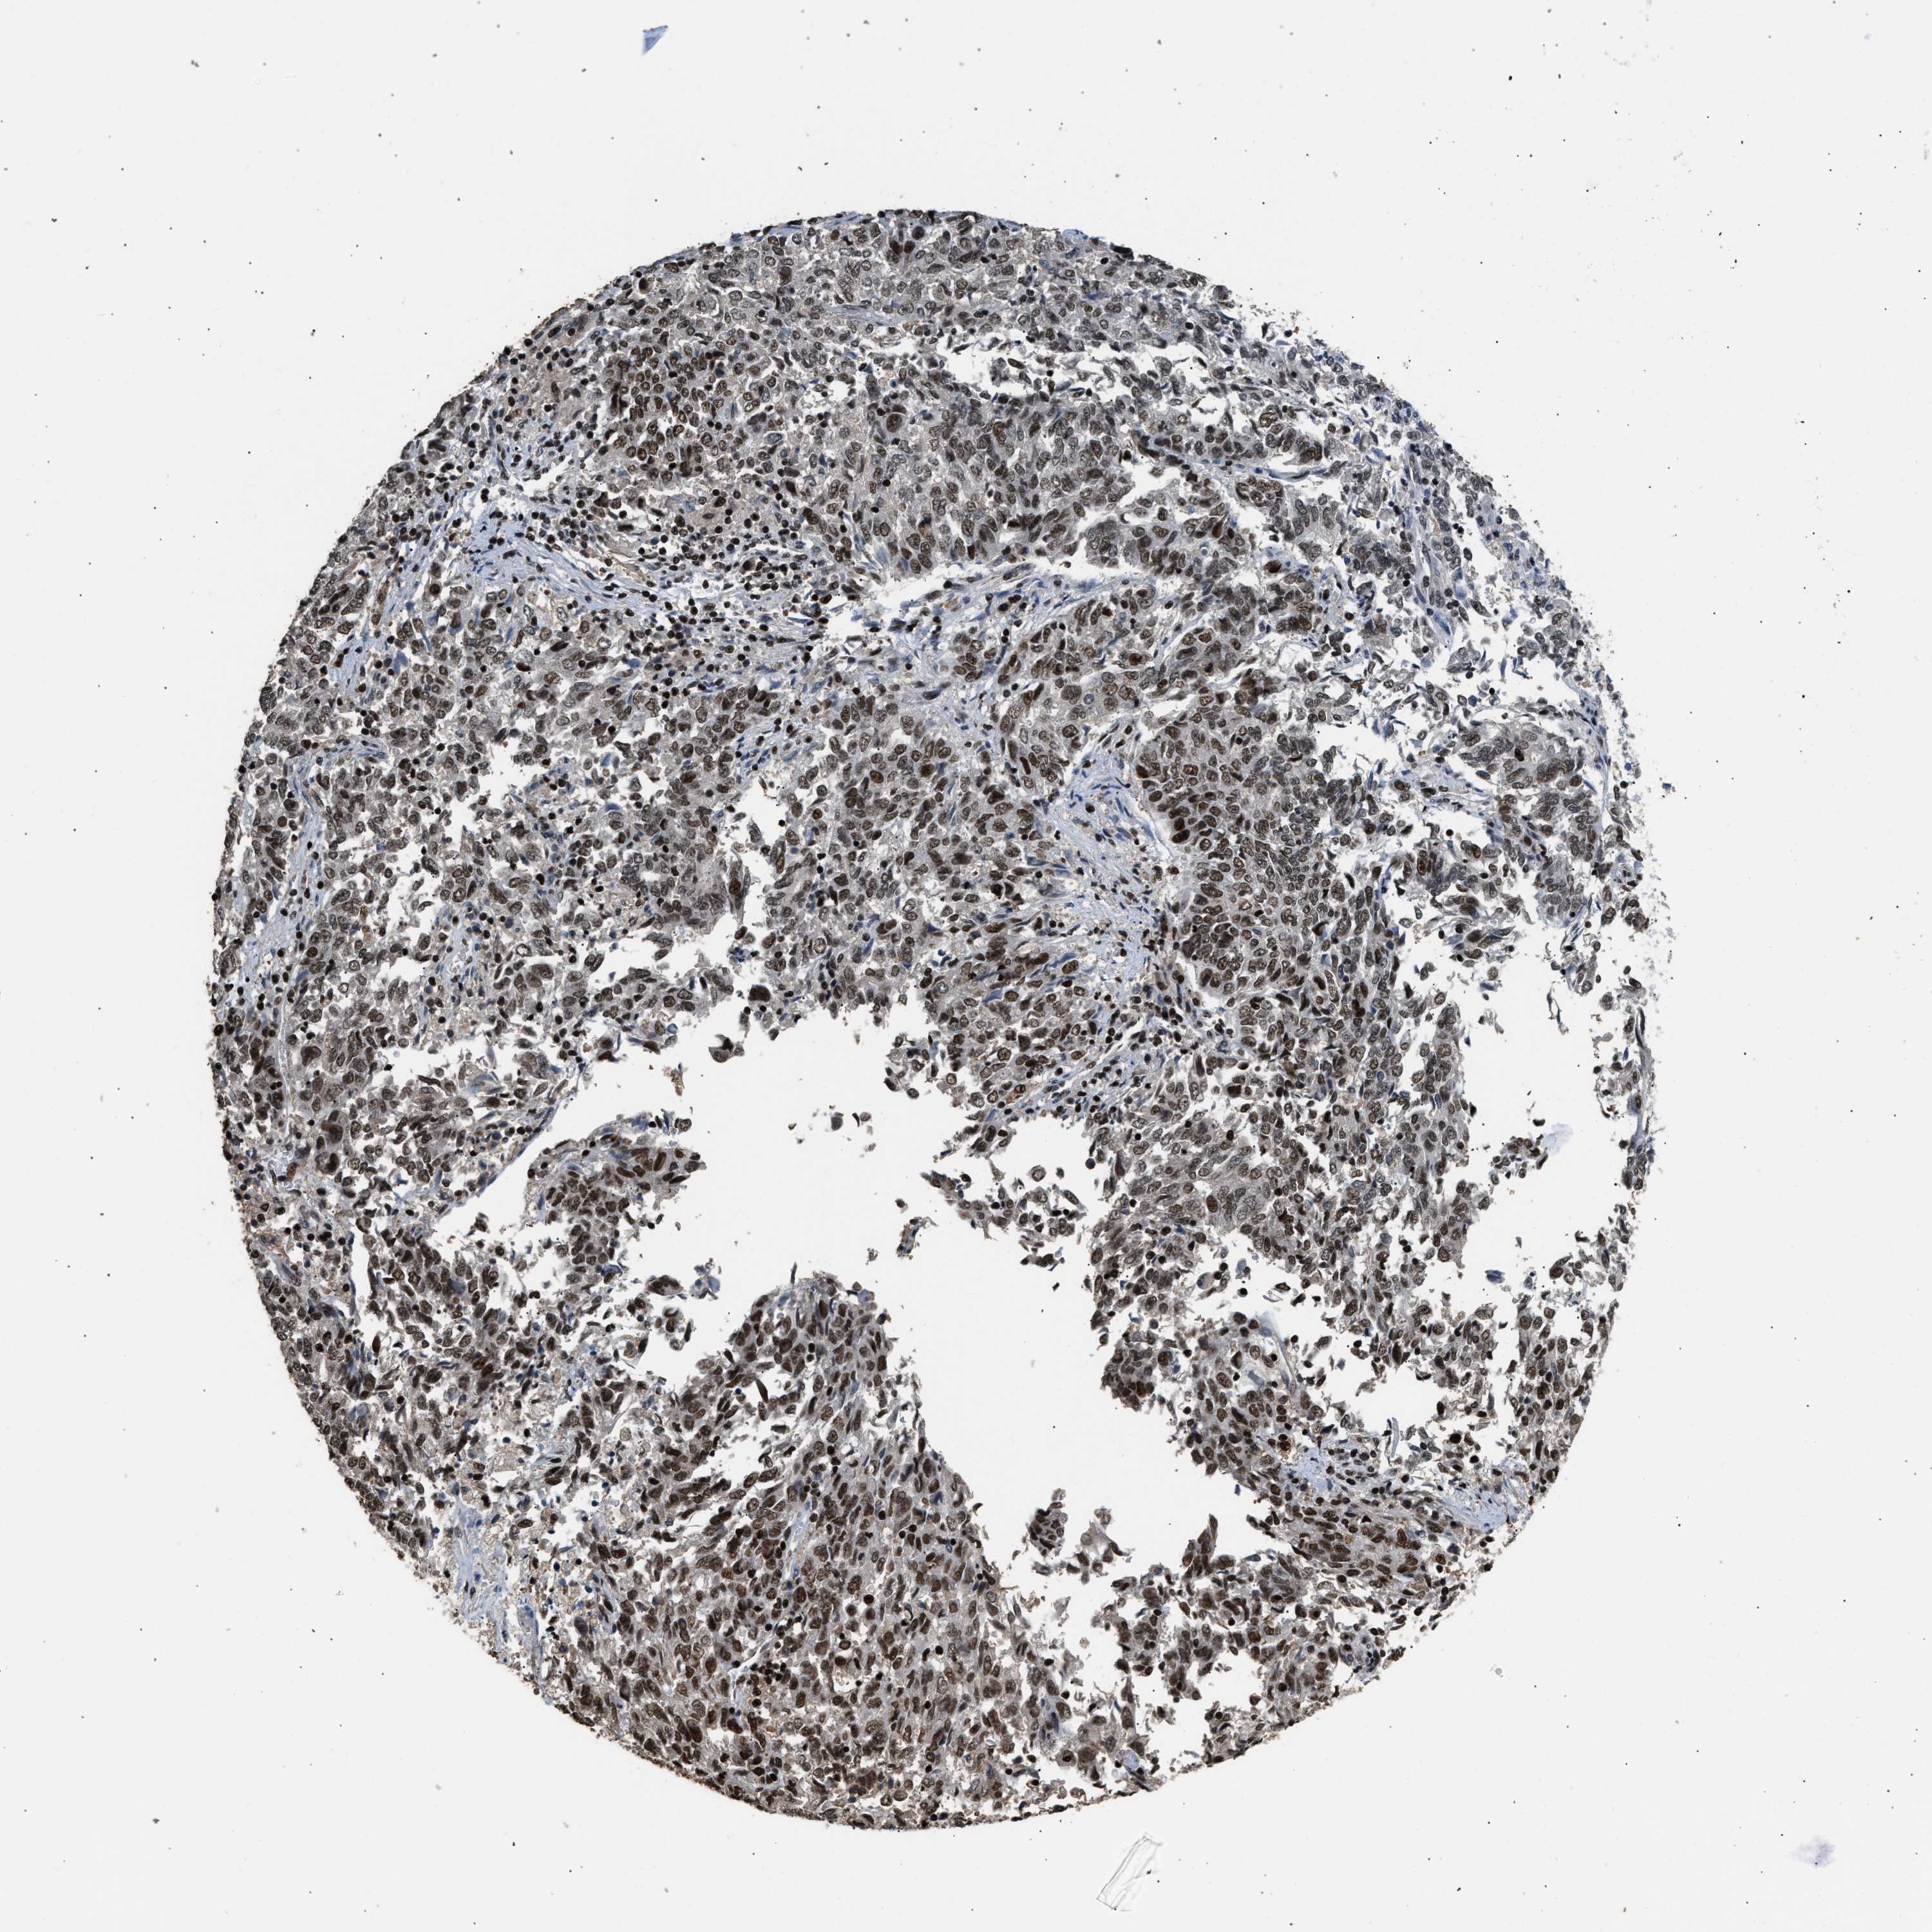

ENDOMETRIAL CANCER - Protein expressioni

A mouse-over function shows sample information and annotation data. Click on an image to view it in a full screen mode. Samples can be filtered based on level of antibody staining by selecting one or several of the following categories: high, medium, low and not detected. The assay and annotation is described here.

Note that samples used for immunohistochemistry by the Human Protein Atlas do not correspond to samples in the TCGA dataset.

Antibody stainingi

Antibody staining in the annotated cell types in the current human tissue is reported as not detected, low, medium, or high, based on conventional immunohistochemistry profiling in selected tissues. This score is based on the combination of the staining intensity and fraction of stained cells.

Each image is clickable and will lead to virtual microscopy that enables deeper exploration of all samples and also displays staining intensity scores, fraction scores and subcellular localization as well as patient and tissue information for each sample.

Antibody HPA020044

Antibody CAB022065

Staining

High

Medium

Low

Not detected

Intensity

Strong

Moderate

Weak

Negative

Quantity

>75%

75%-25%

<25%

None

Location

Nuclear

Cytoplasmic/membranous

Cytoplasmic/membranous,nuclear

Adenocarcinoma, NOS

Adenoma, NOS